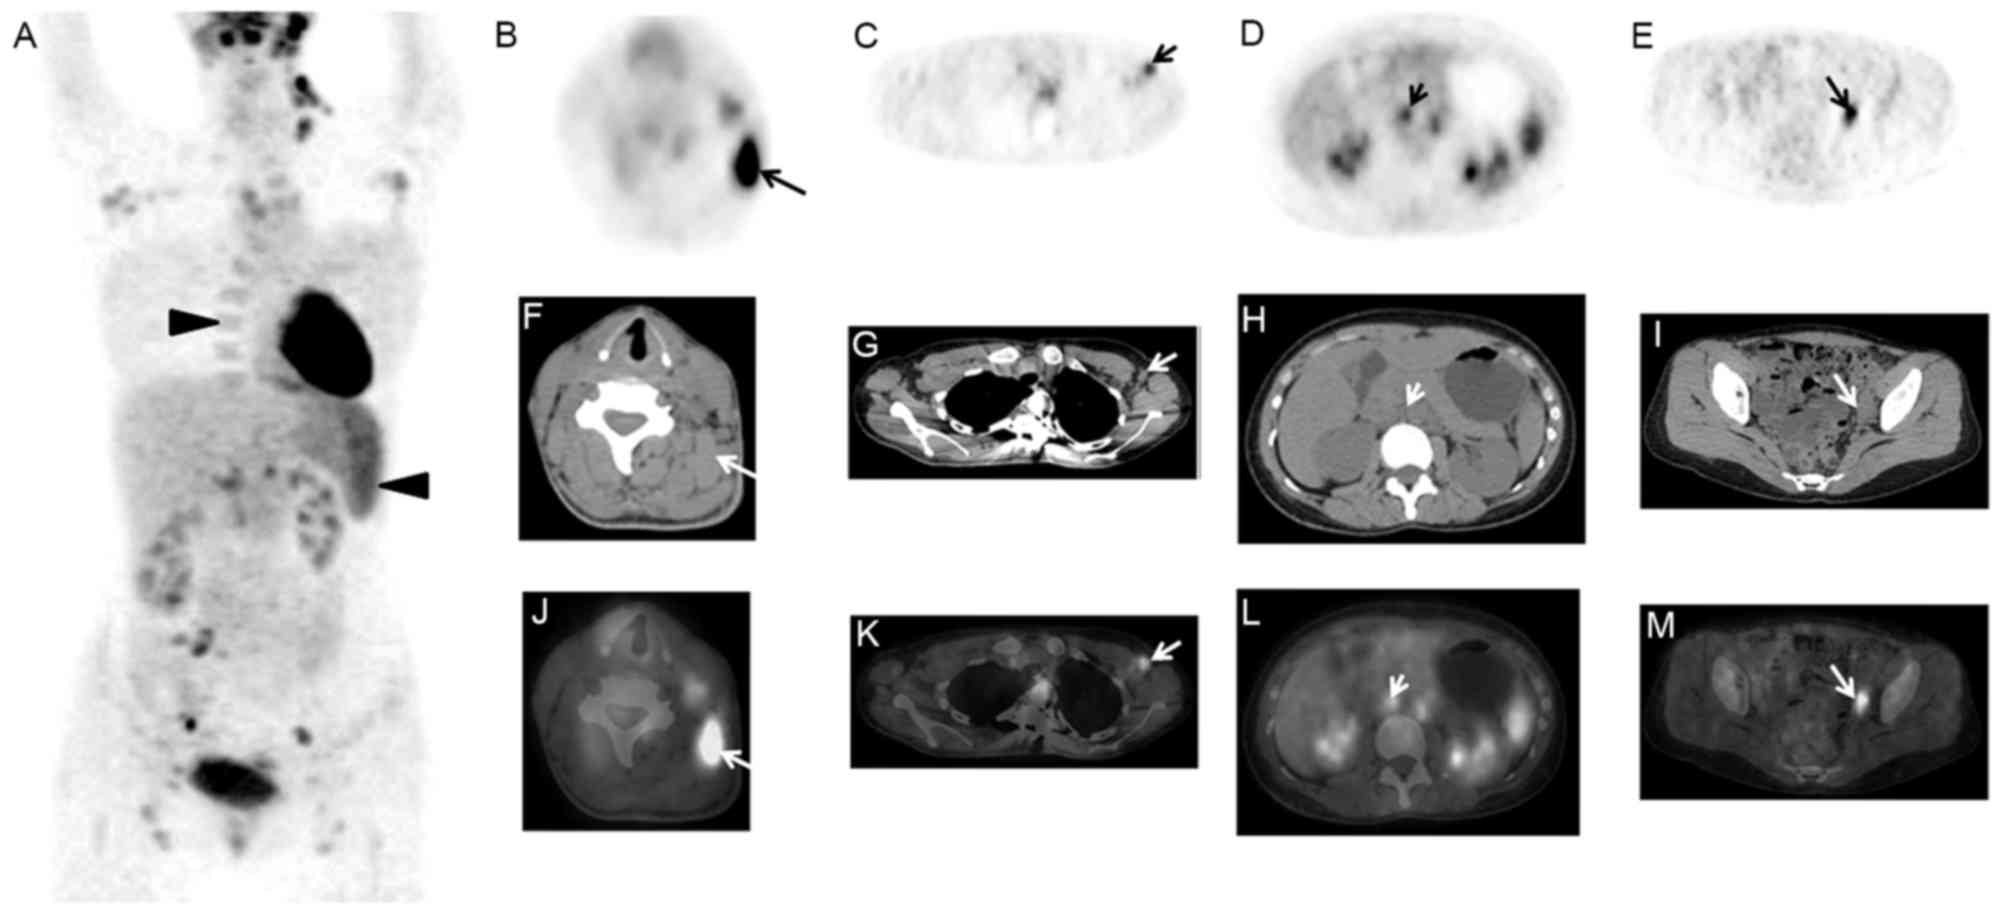

Based on the imaging features of this study, the roles of 18F-FDG PET/CT in AOSD were retrospectively investigated. Firstly, 18F-FDG PET/CT could display both anatomic and functional changes of AOSD, and evaluated the involved extent of AOSD. For example, as presented in Fig. 3, the case only displayed diffusely elevated FDG activity in bone marrow of whole body on PET/CT images. The case in Fig. 4 demonstrated that although multiple enlarged lymph nodes of the whole body with mildly increased radioactivity were displayed on PET/CT images, the benign diseases of lymph nodes such as inflammation rather than malignancies were diagnosed based on the size, morphology, density, and SUVmax of the lymph nodes in this case. However, for other cases, as presented in Figs. 5 and 6, which was difficult to make differential diagnosis with lymphoma. Secondly, it could guide the biopsy of tissues with abnormal FDG accumulation including lymph nodes, bone marrow, skin and other tissues. Regarding the cases in Figs. 5 and 6, the biopsies of the lymph nodes were performed under the guide of 18F-FDG PET/CT imaging, which contributed to suggest the proper lymph node applied for the biopsy. Finally, 18F-FDG PET/CT is helpful in the post-treatment evaluation of AOSD. Although these data weren't investigated in the present study, Choe et al (2) and Yamashita et al (17) identified significant improvements (decreased SUV level) in the initially abnormally sized radioactive lesions in the follow-up images of PET/CT.

Figure 4.

A 28-year-old female presented with intermittent fever, bilateral knee joints pain, and rash for 1 month, and Tmax was 40.4°C. The treatment of antibiotics was invalid, and local CT displayed multiple enlarged lymph nodes of cervical and axillary regions. 18F-FDG PET/CT scan indicated that the spleen was markedly enlarged with FDG accumulation, with SUVmax of 5.2, and diffuse radioactivity uptake was observed in the bone marrow with an SUVmax of 5.0 (A: MIP, triangle arrows). In addition, multiple lymph nodes of cervical, supraclavicle, mediastina, axillary, abdominal, retroperitoneal, pelvic and inguinal regions were enlarged with increased radioactivity (B-D: PET, E-G: CT, and H-J: PET/CT, arrows). CT, computerized tomography; 18F-FDG, fluorodeoxyglucose; PET, positron emission tomography; SUV, standardized uptake value; MIP, maximum intensity projection.

Figure 5.

A 25-year-old female presented with a mass located in the left cervical region for 1 month, fever (Tmax of 40.0°C) and joint pain for 3 weeks. The patient had history of corrective operation for deformities of the spine 10 years ago. 18F-FDG PET/CT imaging displayed that in addition to diffuse FDG uptake by the spleen and bone marrow (A: MIP, triangle arrows), multiple lymphadenopathy with abnormal FDG uptake (arrows) was observed (B-E, PET; F-I, CT; and J-M, PET/CT). The biopsy of left cervical lymph node (B, F and G; arrows) was taken and the pathology was non-specific inflammation. The biopsy of bone marrow was non-specific reactive hyperplasia of hematopoietic cells. After the therapy of CSs for 1 month, ultrasound displayed that the lymph nodes of left neck and axillary obviously shrine. 18F-FDG, fluorodeoxyglucose; PET, positron emission tomography; CT, computerized tomography; MIP, maximum intensity projection.